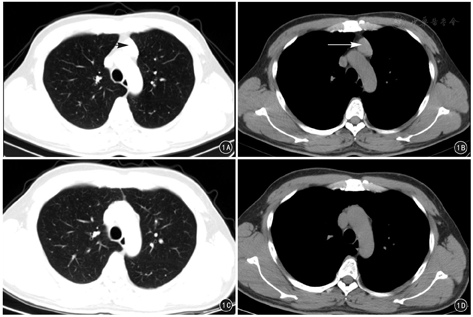

20例患者术后均获随访,随访时间3~24个月,平均11个月。术后1~2个月常规复查胸部CT,均无纵隔脂肪软组织影残留。随访期间2例合并重症肌无力的胸腺瘤患者,肌力恢复满意,日常生活可自理;1例术后3~6个月,口服溴比斯的明剂量逐渐减至术前1/2,1例术后12个月,口服药物剂量较术前减少1/3。典型病例见图1。